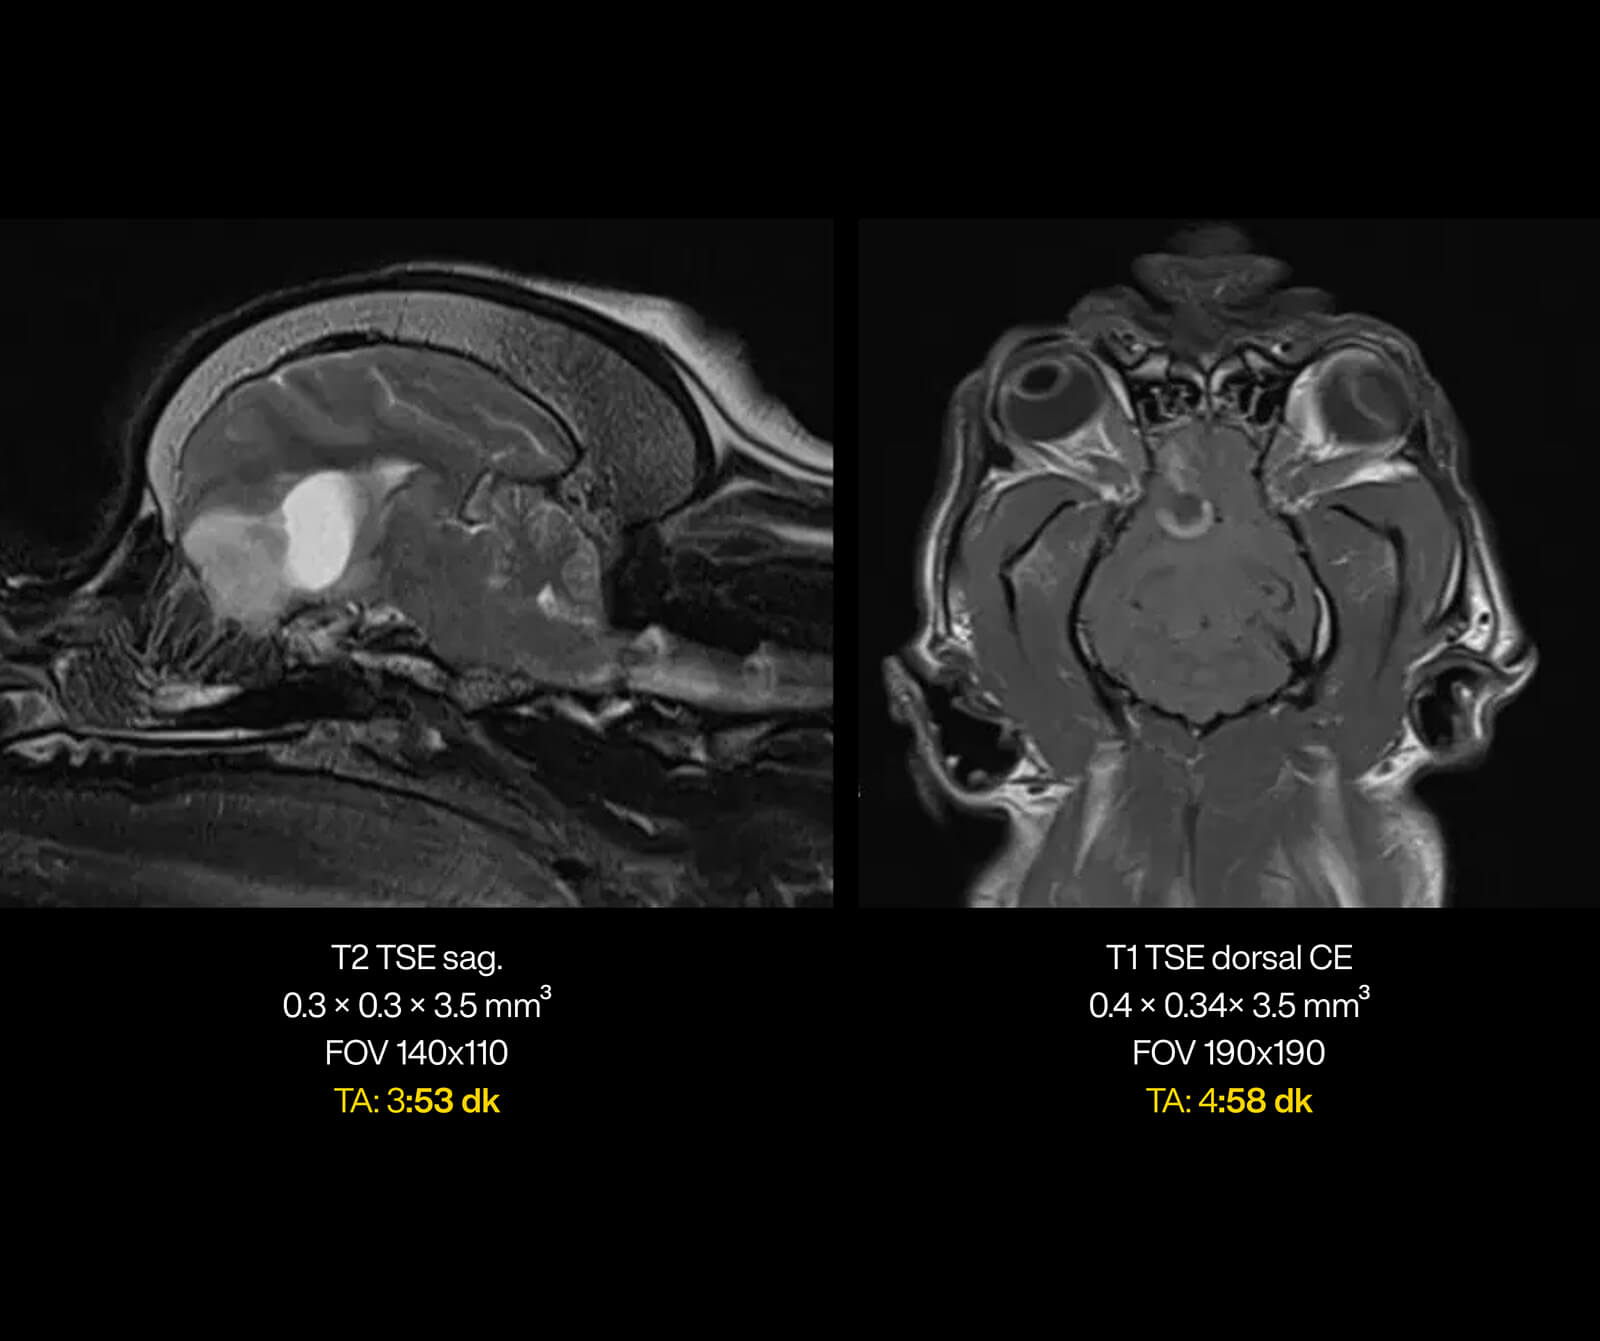

Merkezimizde, süper iletken magnet teknolojisine sahip, yapay zekâ destekli Manyetik Rezonans (MR) sistemleri kullanılmaktadır. Veteriner hekimlik ihtiyaçlarına özel olarak optimize edilmiş bu ileri teknoloji sistemler; yüksek görüntü kalitesi ile hasta güvenliğini birlikte hedefleyen bir altyapı sunar.

Yapay zekâ destekli yazılım ve rekonstrüksiyon teknolojileri, görüntüleme sürecinin planlanması, ham verilerin işlenmesi ve görüntülerin yeniden oluşturulması aşamalarında aktif olarak kullanılmaktadır.

Bu sayede:

• Görüntü gürültüsü azaltılır,

• Kesitsel ve uzaysal çözünürlük artırılır,

• Hareket artefaktları minimize edilir,

• Daha kısa sürede daha yüksek tanısal değere sahip görüntüler elde edilir.

Bu teknolojik altyapı sayesinde geniş görüntüleme alanlarında dahi yüksek çözünürlük ve detaylı kesitsel görüntüler sağlanırken, sevimli dostlarımızın anestezi altında geçirdiği süre optimum düzeyde tutulur ve tanısal doğruluk en üst seviyeye çıkarılır.